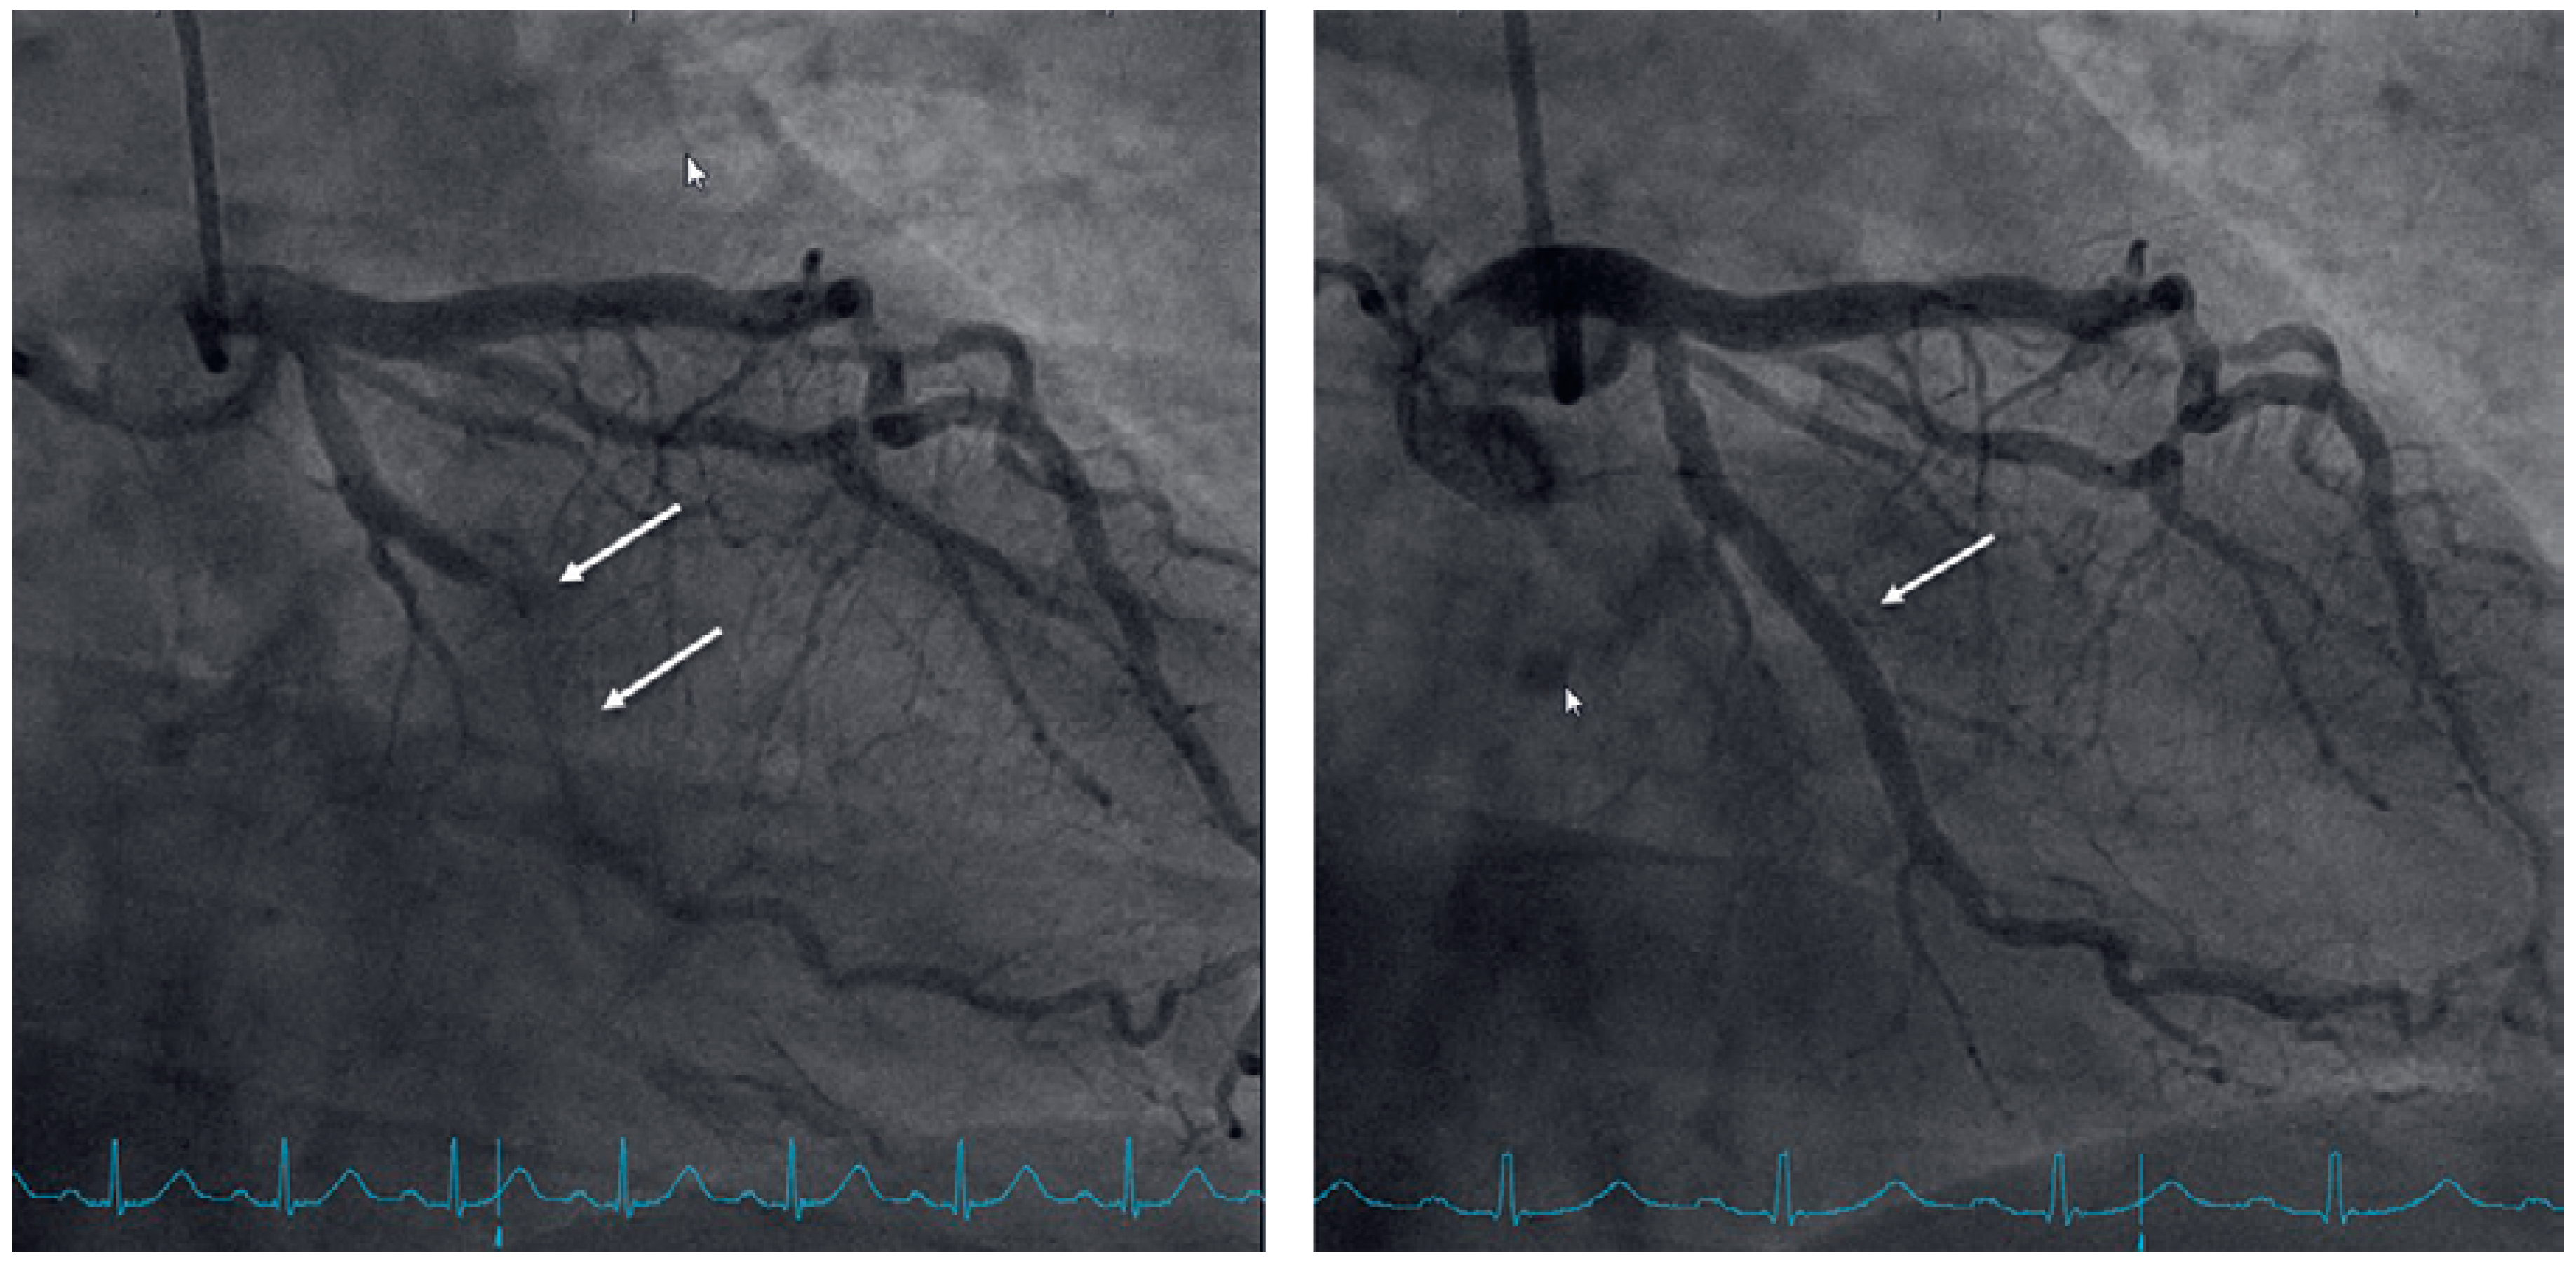

To exclude coronary artery disease the patient was referred for a cardiac single photon emission computed tomography (SPECT) scan using technetium-99m, which revealed a normal radionuclide tissue distribution at rest, but after physical stress using a bicycle ergometer significant left ventricular inferior-lateral ischaemia of 10–15% was observed (Figure 2). Elective coronary angiography confirmed coronary artery disease with chronic total obstruction of the left circumflex artery. One drug-eluting stent was placed successfully (Figure 3).

Figure 3. Right anterior oblique projection of the left circumflex artery before (left) and after (right) placement of one drug-eluting stent.